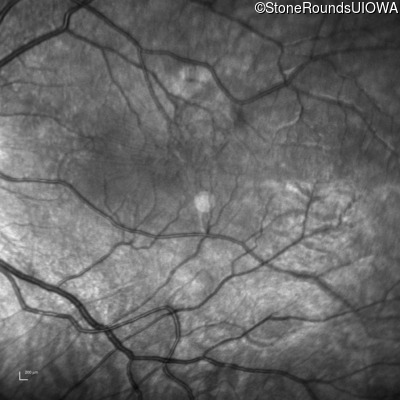

This 9 year old male was noted to have some crossing of his eyes at 2 months of age and the eye exam which followed identified a retinal lesion in the right eye. When he was six years old an epiretinal membrane was noted in his left eye. Two years later it was decided that it was a thin hamartoma in that eye as well. He underwent neuroimaging at age 7 which identified bilateral acoustic neuromas.

| Age at visit: 8 years |

| Age at visit: 10 years |

| Age at visit: 11 years |

| Age at visit: 14 years |